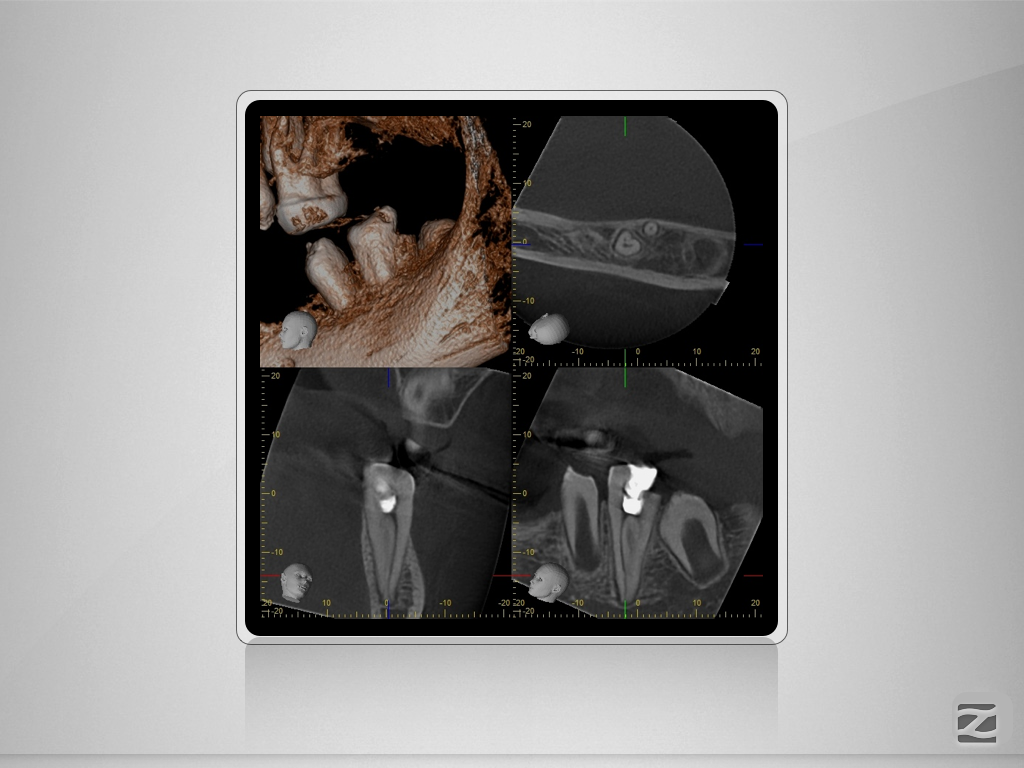

36D.005

1024 × 768

Doppeltes C